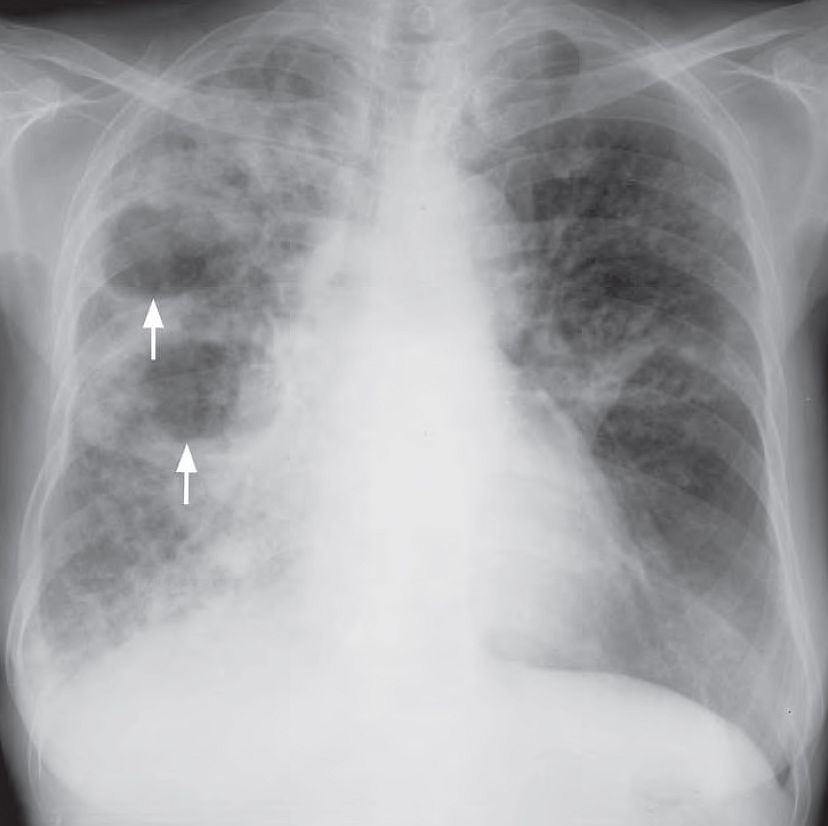

- Multiple areas of air-space opacification in the right lung also involving the apex

- Cavitation and air-fluid level within the opacified areas

- Blunting of right CP angle due to exudative effusion

Diagnosis: Caseous Necrosis in Tuberculosis